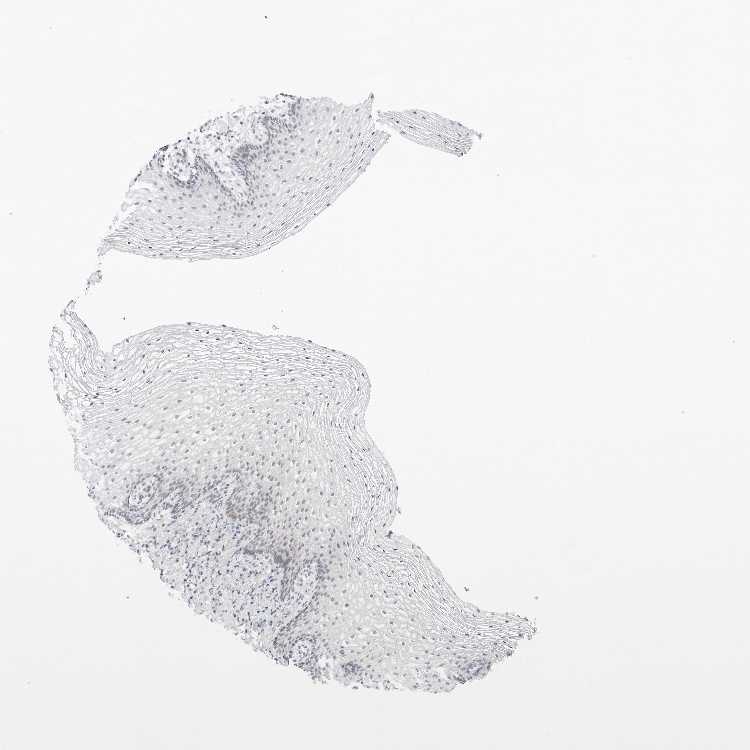

TISSUE PRIMARY DATA VAGINA Show tissue menu

Vagina

VAGINA - Antibody stainingi

Antibody staining in the annotated cell types in the current human tissue is reported as not detected, low, medium, or high, based on conventional immunohistochemistry profiling in selected tissues. This score is based on the combination of the staining intensity and fraction of stained cells.

Each image is clickable and will lead to virtual microscopy that enables deeper exploration of all samples and also displays staining intensity scores, fraction scores and subcellular localization as well as patient and tissue information for each sample.

Antibody HPA027120Antibody HPA027125Antibody HPA027268

Squamous epithelial cells MediumMediumNot detected